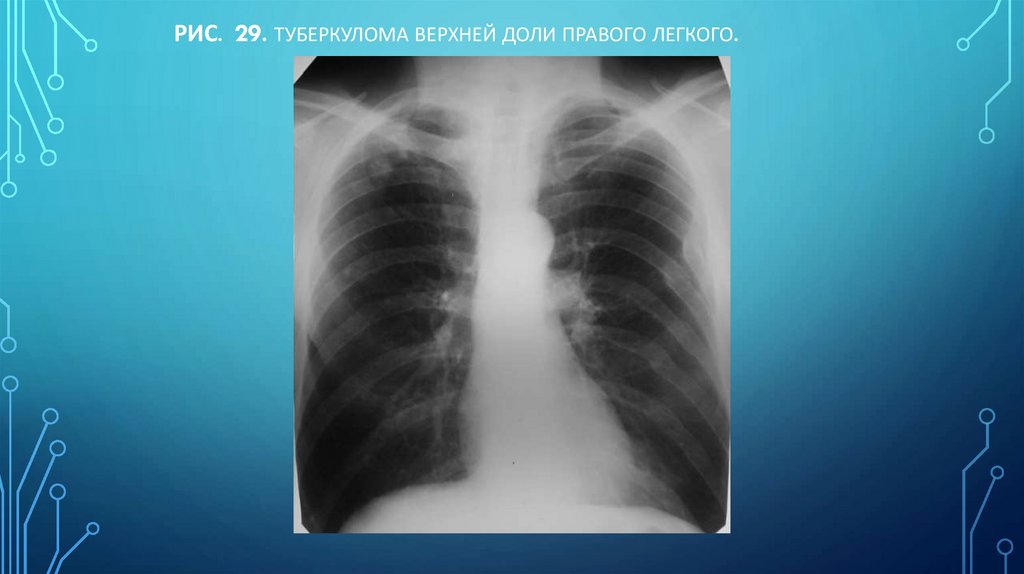

Рис. 29. Туберкулома верхней доли правого легкого.

98. Рис. 29. Туберкулома верхней доли правого легкого.

Туберкулома характерны мелкие обызвествления в разных ее участках

III. Круглая тень

Туберкулома